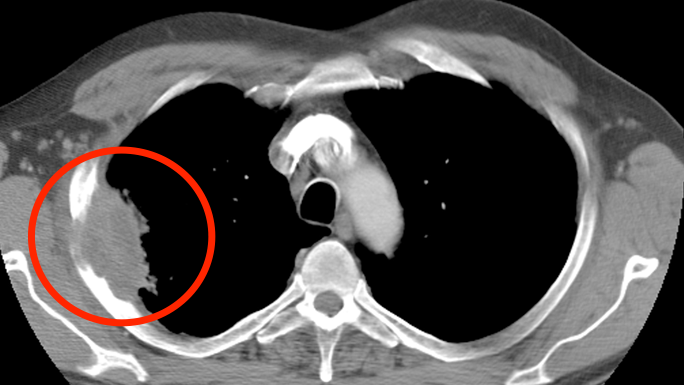

Lung cancer ct scan images. For a bone scan a small amount of low level radioactive material is injected into the blood and collects mainly in abnormal areas of. Although the ct scan cannot give a definitive diagnosis it is helpful in the evaluation of lung diseases and conditions such as pneumonia cancer blood clots or damage caused by smoking. Lung cancer is the top cause of cancer deaths in both men and women. The primary tumor shows a wide spectrum of imaging appearances. Although ct scan imaging is best imaging technique in medical field it is difficult for doctors to interpret and identify the cancer from ct scan images. Most doctors do not recommend petct scans for routine follow up of patients after lung cancer treatment. However early diagnosis and treatment can save life. The clear white stripes branches and spots are blood vessels. Computed tomography ct scan of the chest is the cornerstone of lung cancer imaging based on which further management is decided. The right side of the lung is on the left side on the picture. Prior to the widespread use of mechanical cigarette rollers lung cancer was. The preprocessed whole lung scan was used as the first input channel for learning.

In diagnosing lung cancer but their role in checking whether treatment is working is unproven. Coloured computed tomography ct scan of a section through the chest of a 76 year old male patient with a malignant cancerous tumour bright right of the bronchus. Learn how lung cancer appears in x rays ct scans and biopsies. But this wasnt always the case. To see the difference between a blood vessel and a nodule you must scroll the pictures in the viewer frequently up and down many times. A ct technician will instruct you to lie flat on the ct scan table which moves quickly through a donut shaped device called a scanner. The bronchi are the airways that carry air to the lungs and mouth. Nsclcs can be centrally located masses invading the mediastinal structures figure 1a or peripherally situated lesions figure 1b that invade the chest wall. Small right upper lung nodulexray of large right lung cancer xray of small left lung cancer xray of lung metastases xray large right lung cancer. Lung cancer is one of the dangerous and life taking disease in the world. Lung cancer images in general a ct scan is much better at finding lung cancers than a chest xray see here here and here also see t stage and node stage see collage of images here chest xrays.